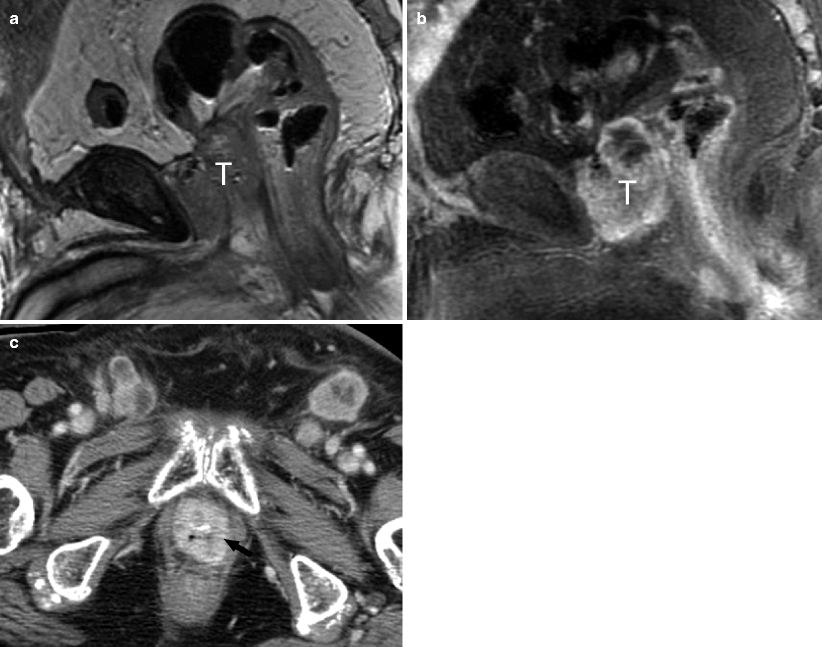

• The Urinary Bladder | Radiology Key - Bladder Cancer Is Any Of Several Types Of Cancer Arising From The Tissues Of The Urinary Bladder.

• Neoplasms Of The Urinary Bladder | Abdominal Key : Therapeutic Efficacy Of Cyclophosphamide As A Function Of Inhibition.

Neoplasms of the urinary bladder | Abdominal Key. For patients given cumulative doses between 20 and 49 g, the absolute risk of bladder cancer is on the order of three. It is a treatment for a number of different types of cancer. Cyclophosphamide (cp), also known as cytophosphane among other names, is a medication used as chemotherapy and to suppress the immune system. As chemotherapy it is used to treat lymphoma, multiple myeloma, leukemia, ovarian cancer, breast cancer, small cell lung cancer, neuroblastoma. Cyclophosphamide is one of these medications. Bladder cancer can affect anyone. Bladder cancer is a common type of cancer that begins in the cells of the bladder. Cyclophosphamide also increases the risk of developing some kinds of cancer, including lymphoma, skin and bladder. Major risk factors include smoking, exposure to certain chemicals, and having a family history of the disease. Symptoms include blood in the urine, pain with urination, and low back pain. Bladder cancer is any of several types of cancer arising from the tissues of the urinary bladder. Cyclophosphamide official prescribing information for healthcare professionals. Cyclophosphamide may result in blood in the urine or scarring of the bladder. Find out more and about side effects. Urotoxicity (bladder ulceration, necrosis, fibrosis, contracture and secondary cancer) may require interruption of.